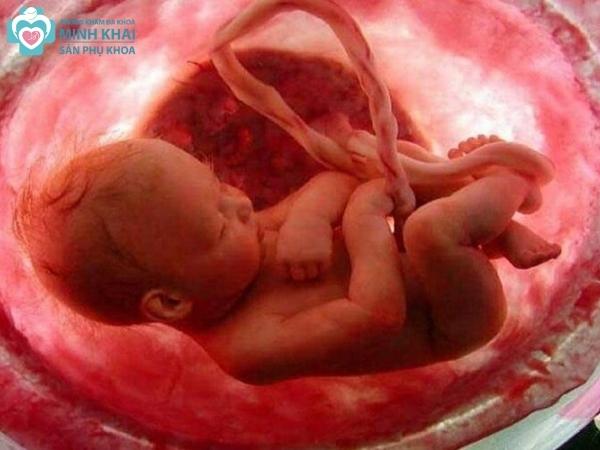

Siêu âm thai 4D dùng đầu máy dò phát sóng âm di chuyển trên thành bụng mẹ để thu lại hình ảnh 3 chiều không gian của em bé. Nó vượt trội hơn kỹ thuật siêu âm 3D ở chỗ có thể thu được lại cử động trong chiều thời gian thực một cách rõ nét, chân thực hơn rất nhiều. Ba mẹ có thể trực tiếp nhìn thấy hình ảnh video của con mình ngay trên màn LED máy tính.

Hơn nữa, kết quả siêu âm 4D còn phản ánh đầy đủ các chỉ số cũng như chi tiết cấu trúc thai nhi. Theo đó, bác sĩ dễ dàng trong việc đánh giá sức khỏe thai kỳ và phát hiện nhanh chóng các bất thường, dị tật bẩm sinh ở trẻ.